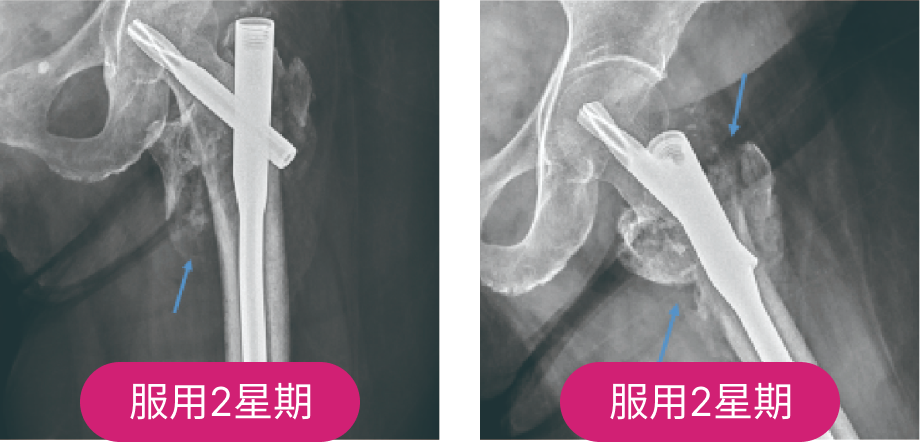

80歲女性

股骨骨折開刀骨癒不良

股骨開刀植入骨髓內釘,經過1個月仍癒合不良

服用非晶鈣骨痂形成

服用2周後骨痂大量形成,加速復原